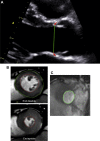

Methods: One hundred thirty-three patients with mild to severe AS and 33 control individuals underwent comprehensive echocardiography and cardiovascular magnetic resonance imaging (MRI). Stroke volume and LVOTarea were calculated using echocardiography and MRI, and the effects on AVA estimation were assessed. The relationship between AVA and MPG measurements was then modelled with nonlinear regression and consistent thresholds for these parameters calculated. Finally the effect of these modified AVA measurements and novel thresholds on the number of patients with small-area low-gradient AS was investigated.

Results: Compared with MRI, echocardiography underestimated LVOTarea (n = 40; -0.7 cm(2); 95% confidence interval [CI], -2.6 to 1.3), stroke volumes (-6.5 mL/m(2); 95% CI, -28.9 to 16.0) and consequently, AVA (-0.23 cm(2); 95% CI, -1.01 to 0.59). Moreover, an AVA of 1.0 cm(2) corresponded to MPG of 24 mm Hg based on echocardiographic measurements and 37 mm Hg after correction with MRI-derived stroke volumes. Based on conventional measures, 56 patients had discordant small-area low-gradient AS. Using MRI-derived stroke volumes and the revised thresholds, a 48% reduction in discordance was observed (n = 29).